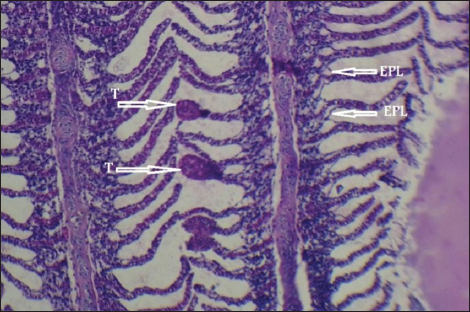

Histopathological findings of gill section showed telangictatisis and epithelial lifting in secondary lamellae (Fig. 7) with hemorrhage and blood congestion (Fig. 8), also, the result showed the central venous dilation with blood congestion and epithelium hyperplasia with complete fusion of the secondary lamellae (Figs. 9 and 10) and edema in the filamentary epithelium (Fig. 11) in addition to mononuclear cells infiltration (Figs. 12 and 13).

Fig. 7. Histopathological sections of gill of C. carpio showing telangictatisis (T) and epithelial lifting (EPL) (H&E X10).

The changes in gill tissue are not exclusive to As, Pb, and Hg toxicity (e.g., telangiectasis, epithelial lifting, hemorrhage, congestion, etc.) which have been previously reported in other stressful situations, like pesticide exposure (Fanta et al., 2003). All of these changes may be defense mechanisms meant to lengthen the time it takes for waterborne contaminants to diffuse and enter the bloodstream (Arellano et al., 1999). With particular reference to exposure to metals, Mustafa et al. (2012) observed telangiectasis, necrosis, in mirror carp C. carpio exposed to Cu, with the epithelium lifted away from the basement membrane. Similar results were also noted in Sole senegalensis, the Senegalese sole, after it was exposed to a sub-lethal concentration of Cu for 7 days (Arellano et al., 1999).